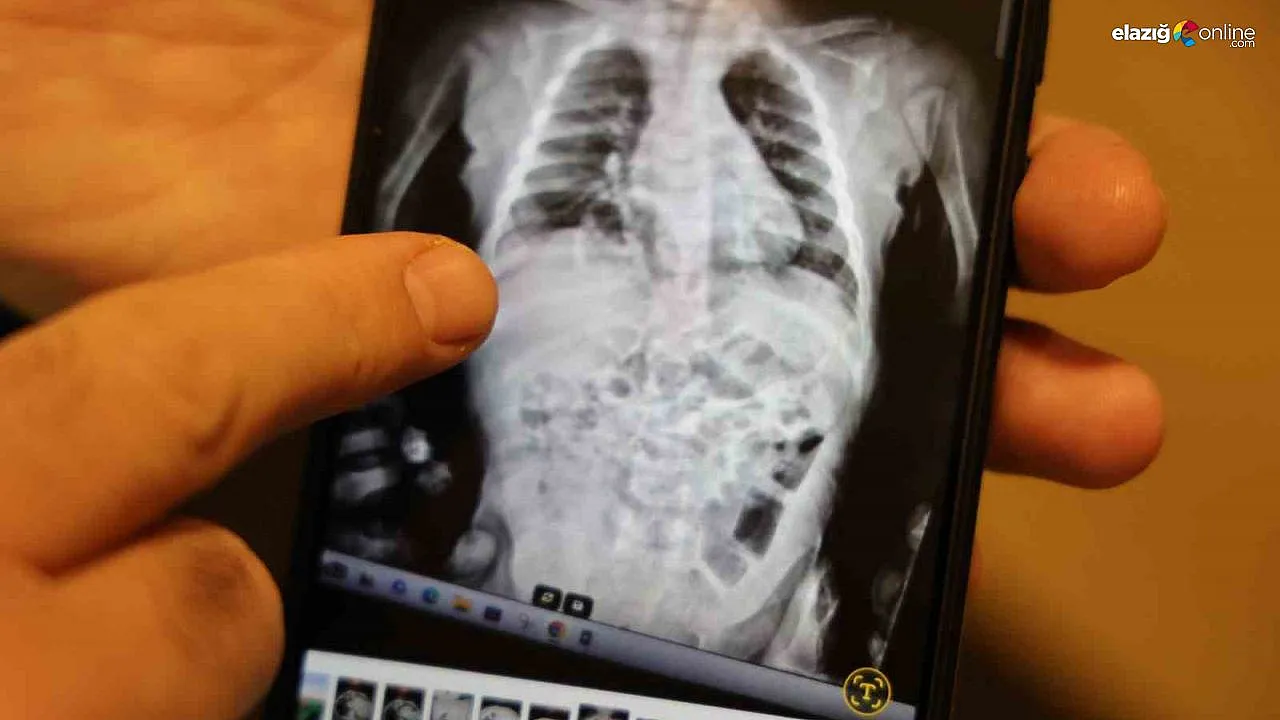

Op. Dr. Taner Kamacı, hastanın diyafram hernesi dedikleri bir rahatsızlıkla kendilerine başvurulduğu söyledi. Hastanın sık sık akciğer enfeksiyonu geçirip ve zatürre nedeniyle tedavi gören bir hasta olduğunu belirten Kamacı, bunları araştırırken çocuğun diyaframında doğuştan gelen bir yırtık olduğu ve bu yırtıktan bağırsaklarının karın içinde olması gerekirken göğüs boşluğuna doğru çıktığı ve akciğeri sıkıştırdığını tespit ettiklerini ifade etti. Kamacı, doğuştan itibaren böyle diyafram yırtıkları olduğuna değinerek, "Bu hastamızın özelliği diyafram fıtıklarının en nadir görülen tipi. Morgagni hernisi dediğimiz özel bir tip. Yaklaşık 200 bin doğumda bir görünen nadir vaka. Türkiye’de geçen sene 937 bin bebek doğmuş. Düşünün bu şekilde Türkiye’de sadece 5 hasta doğuyor bir yıl içinde. Akciğer filmleri ve tomografisiyle teşhisini koyduk" dedi.

Kapalı laparoskopik yöntemle ameliyatı yaptıklarını kaydeden Kamacı, "Ameliyatta göğüs boşluğuna çıkan bağırsakları karnın içine geri indirdik. Diyaframda olan yırtığı ya da fıtık kısmını dikerek kapalı yöntemle kapatıyoruz. Yaklaşık 1 saat süren bir ameliyatla hastamızı tedavi ettik. Bir sonraki gün de hastamızı taburcu ederek evine gönderdik. Bugün hastamızın kontrolünü yapıyoruz. Kontrolünde de her şey yolunda görünüyor. Fıtığında her hangi bir sıkıntı yok. Bundan sonra akciğer enfeksiyonu geçirmeden tamamen normal hayatına dönecek" şeklinde konuştu.